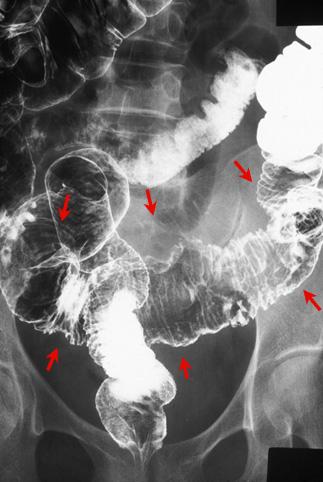

Criteria of Hist.ClassificationMalignant epithelial tumor/Adenocarcinoma

LocationLarge intestine(Colon)/Sigmoid colon

Technique, MethodX-ray

Macroscopic TypesType 5 Unclassfied type/

Size40 -

Depth of Tumor Invasionsubserosa (subadventitia)